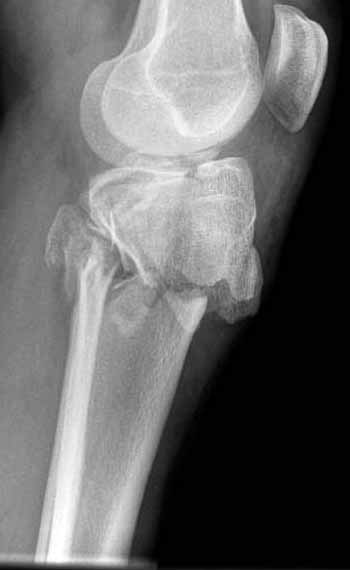

Двухколоннный перелом тибиал плато с вовлечением проксимального диафиза. Внутрисуставной компонент без смещения, и такой перелом можно лечить любым из описанных методов, о которых говорят наши коллеги.

Как понял, аппарат Илизарова не рассматривается предпочтительным для фиксации методом, хотя на фоне отека было бы идеальным для данного перелома. Для пластины требуется идеальная кожа, иначе наличие “суперсовременных имплантов” не поможет, и могут развиться серьезные осложнения.

В основном пластины рассчитаны на латеральную поверхность, потому что с латеральной стороны больше мягкотканая подушка, а также через латеральную колонну проходит ось конечности, что немаловажно в удержании оси от деформации.

Для изолированных переломов медиального тибиал плато, фиксацию можно провести “медиальной пластиной”. Некоторые компании, например Smith & Nephew делают медиальные и медиально-задние пластины, но они мягкие, и легко можно создать нужный контур. Жесткость создается за счет фиксации жесткими пластинами, например экстра артикулярной пластиной для дистального плеча от Synthes. Медиальный доступ тоже не из легких, надо работать между pes and medial gastroc.

Частая ошибка, когда фиксацию двух колонного перелома проводят одиночной пластиной, т.е с одной стороны, и такая фиксация не удерживает, происходит вторичноое смещение. Необходимо нейтрализовать второй пластиной или дополнительным наружным фиксатором.

Если у вас, кроме пластины, нет другого альтернативного варианта, тогда, учитывая мягкотканые проблемы с наружной стороны, я бы рекомендовал операцию делать в два этапа. Преимущества, сперва репозиция и фиксация перелома с медиальной стороны, а затем, после улучшения состояния мягких тканей, зафиксировать с латеральной стороны. Современные пластины имеют латеральный Jig для перкутанных мини доступов.